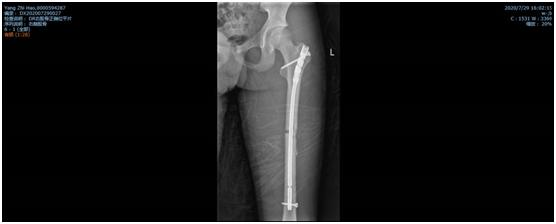

经过骨二科全科人员的商讨后,全麻下行闭合复位髓内钉内固定术的手术方案基本确定。但就国内目前而言,有关髓内钉固定治疗骨骼未成熟的股骨干骨折的疗效研究的样本较小。而且,孩子身高仅160cm,形体偏瘦,测量股骨髓腔最细处约6-7mm,而成人最细髓内钉髓直径大约9mm,无法使用。王钦楠主任积极联系厂家及器械公司,适合的髓内钉终于及时到位,在克服一系列困难及相关科室的支持下,作为威海市首例、山东省第二例同类手术,顺利完成,患者目前已开始负重功能锻炼,病情恢复良好。

双侧股骨干骨折术后照片